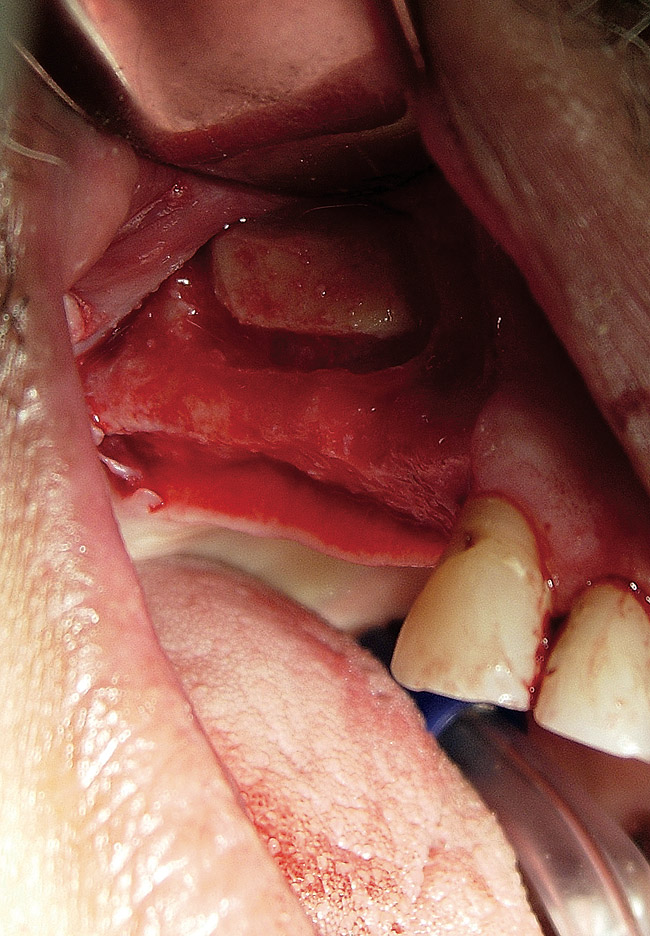

Figure  2  Outline of the lateral window

Figure 2